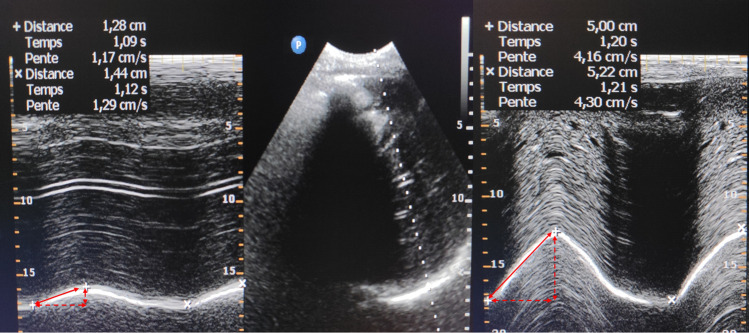

The excursion of both hemidiaphragms was measured sequentially in each patient at two different time points: preoperatively (the day before surgery) and from the seventh postoperative day in patients breathing without assistance (extubated or on pressure support mode with zero PEEP); if patients were not breathing without assistance, the ultrasound evaluation was deferred. In case of respiratory failure with clinical suspicion of DD, a supplementary echography evaluation was performed before the seventh postoperative day. Ultrasound examinations of diaphragm excursion were performed at the bedside with the patient in a 45° semirecumbent position during quiet and unassisted breathing, using an ultrasound platform (Philips CX50®, Amsterdam, The Netherlands) connected to a 1–5-MHz phased-array transducer. Diaphragm excursion was evaluated at rest and after a sniff test, using anatomical motion (M)-mode through a lateral approach from the midaxillary line.14,19 As an exploratory measurement, we also examined the value of each hemidiaphragm peak after the sniff test using tissue doppler imaging velocity. The excursion value of each hemidiaphragm was the average measurement of three consecutive respiratory cycles (separately at rest and after the sniff test) (see example on Fig. 1). Diaphragm dysfunction after the seventh day after cardiac surgery was defined, in M-mode, by a decrease in amplitude of the movement of the diaphragm below the lower limit of normal for at least one of the following measurements: 1) at rest, < 9 mm for women and < 10 mm for men; and 2) after the sniff test, < 16 mm for women and < 18 mm for men.20

Fig. 1.

Right hemidiaphragm ultrasound. Visualization of the right hemidiaphragm in B-mode from the subcostal view (Panel B). Then, application of an M Mode to record diaphragm motion. Panel A shows normal inspiratory diaphragm excursion at rest while panel B shows normal inspiratory diaphragm excursion after the sniff test.